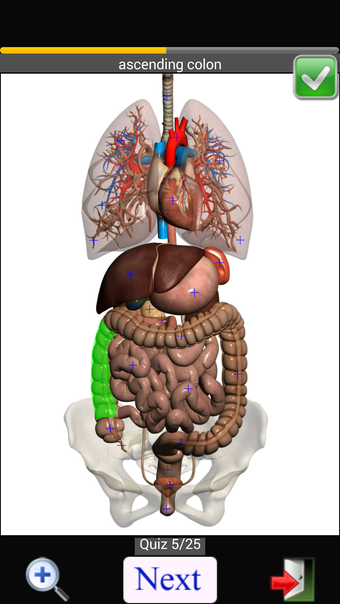

Anatomy Quiz Free es una aplicación de Android de Education Mobile que ofrece una amplia gama de cuestionarios para ayudar a los usuarios a aprender anatomía humana. La aplicación cuenta con más de 500 cuestionarios que ponen a prueba tu capacidad para identificar la ubicación correcta de un objeto dado su nombre. Los cuestionarios se generan a partir de modelos de anatomía 3D virtuales, lo que los hace más atractivos e interactivos. La aplicación es gratuita y no hay versiones premium ni compras dentro de la aplicación.

La aplicación es compatible con los idiomas inglés, francés, español y alemán, lo que la hace accesible para usuarios de diferentes partes del mundo. Las imágenes de alta resolución son nítidas y claras, y la función de zoom con pellizco te permite acercar y alejar las imágenes para una mejor vista. El cuestionario de posición viene con un temporizador, lo que lo hace más desafiante y emocionante. Además, la aplicación tiene una función de transferencia a la tarjeta SD, lo que facilita su transferencia a otros dispositivos.